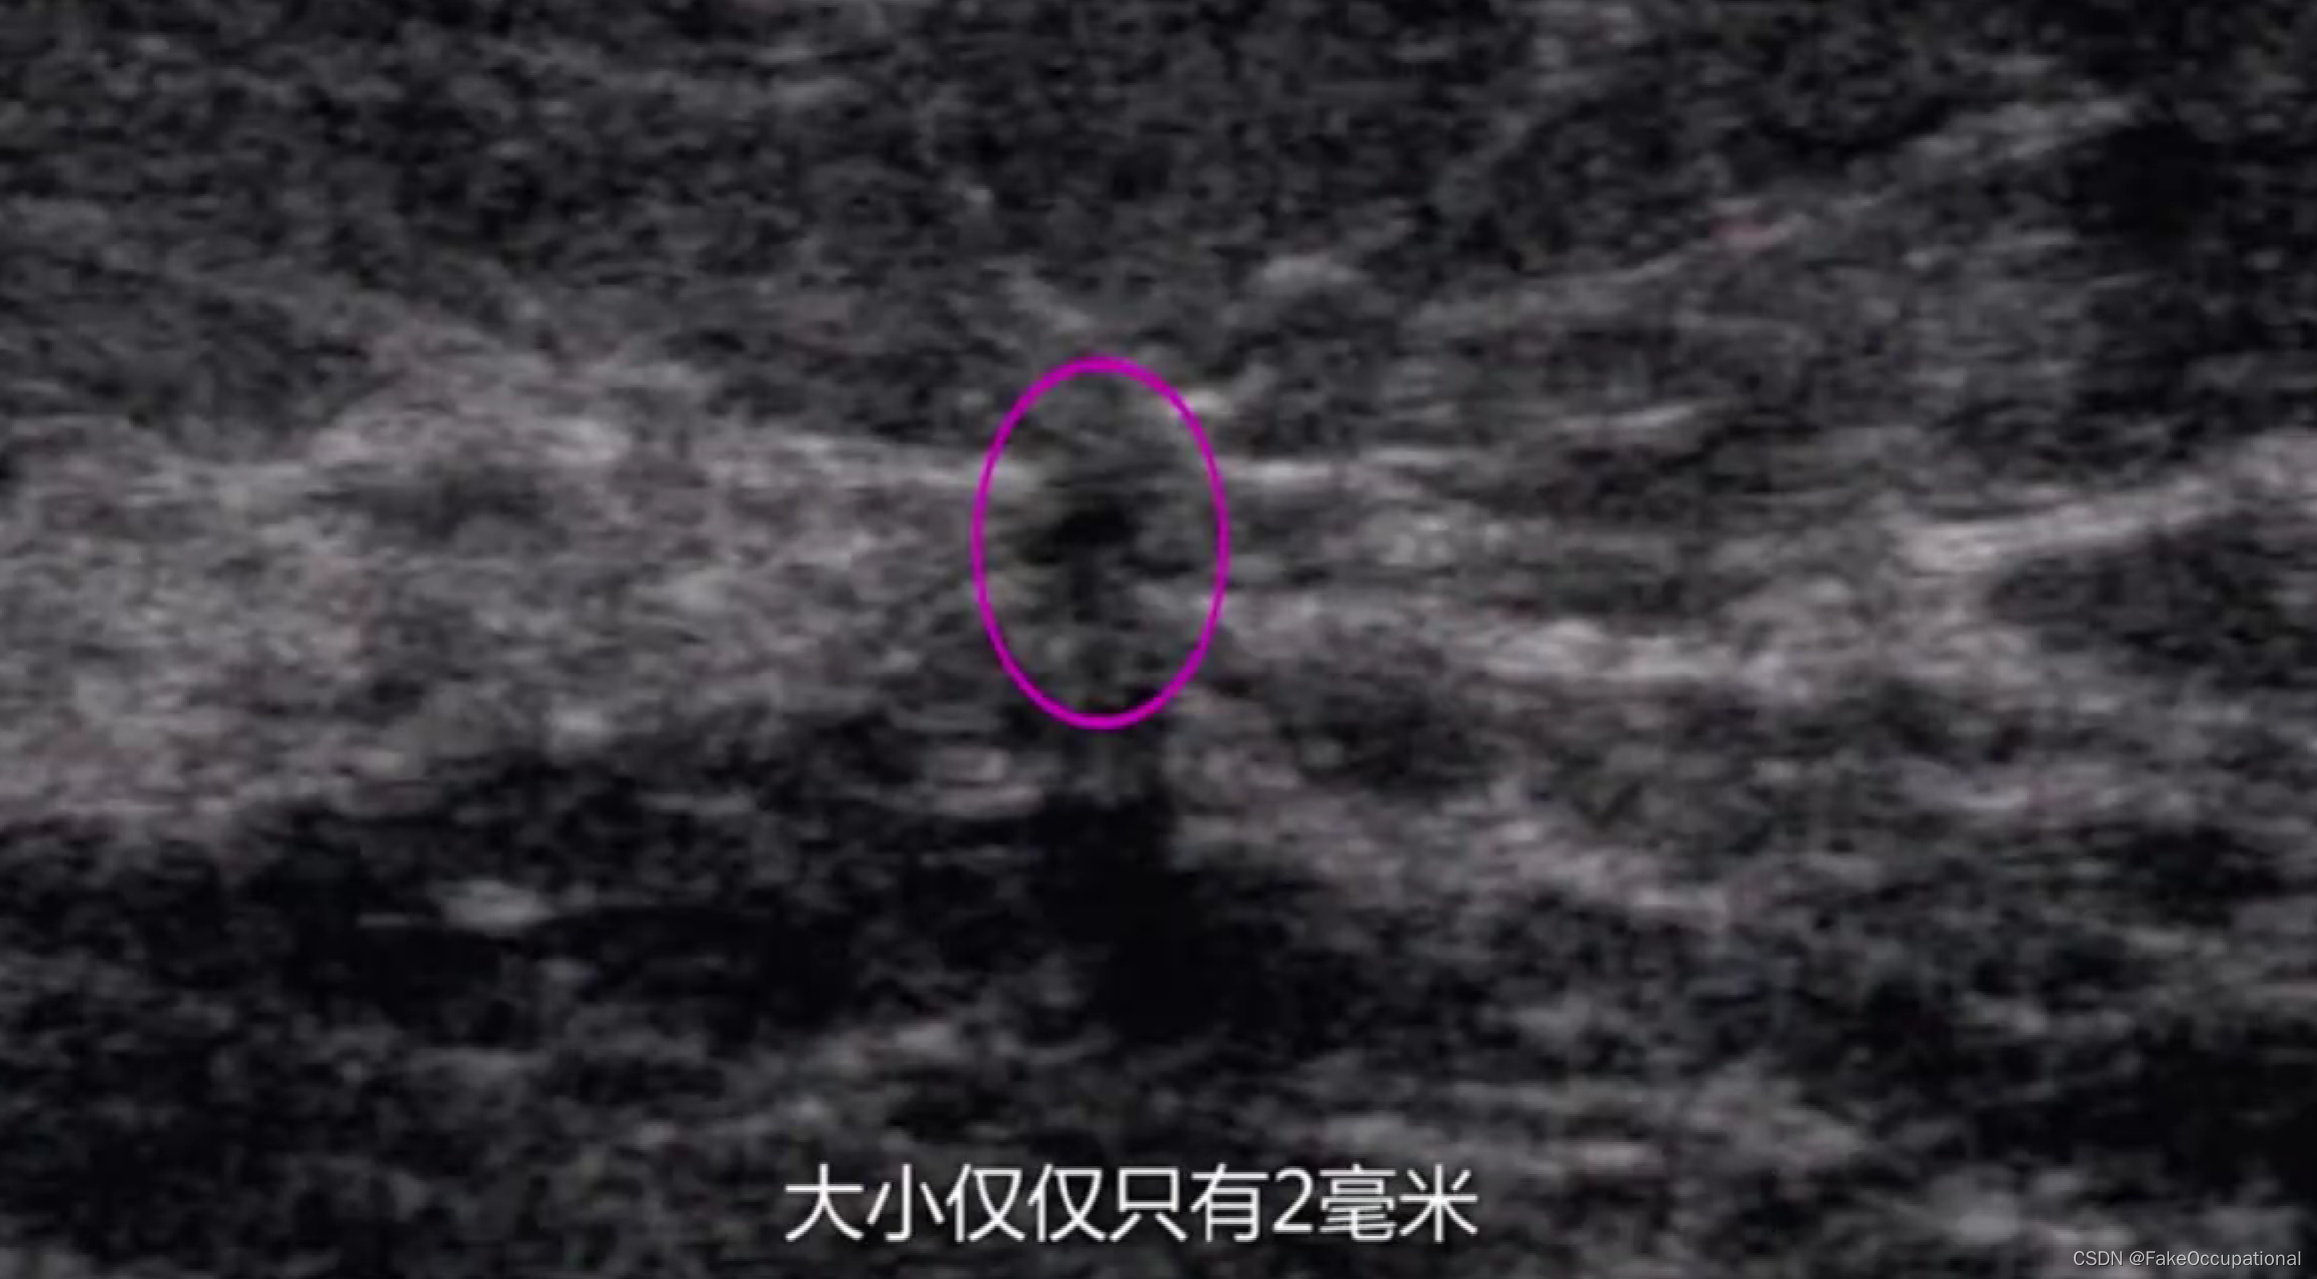

- 患者18岁,微小癌